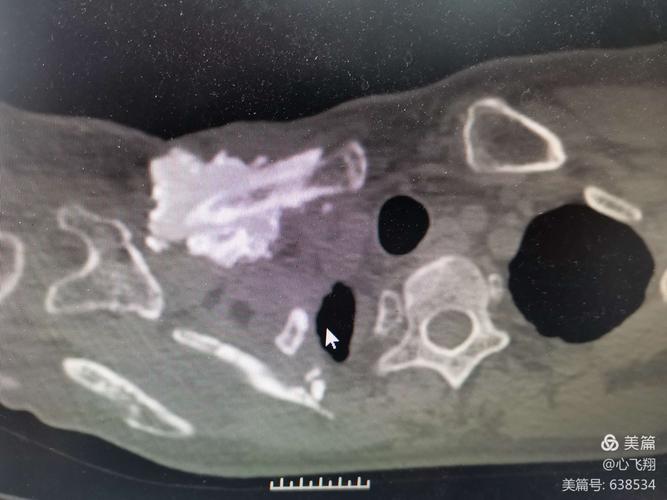

乳腺癌骨转移

乳腺癌骨转移图片

肺癌骨转移ct图片

骨转移ct